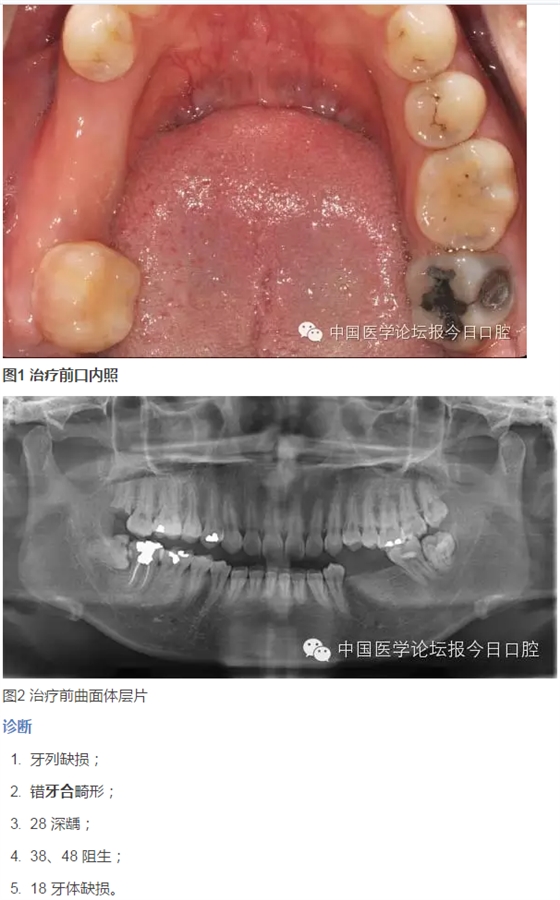

臨床檢查

患者臉型不對(duì)稱,右側(cè)大于左側(cè)。

牙周情況尚可,有少量牙結(jié)石,牙齦無(wú)明顯紅腫。35、36 缺失,25、26 過(guò)長(zhǎng),17 與47,27與37正鎖牙合,咬合時(shí)26、27 的牙尖頂?shù)綄?duì)頜缺牙區(qū)牙槽嵴黏膜上。37、47死髓牙。

全口曲面體層片顯示:35、36缺失,缺牙區(qū)牙槽骨有足夠的骨高度,47未行根管治療,38、48近中阻生,18殘根,28頰面深齲近髓。